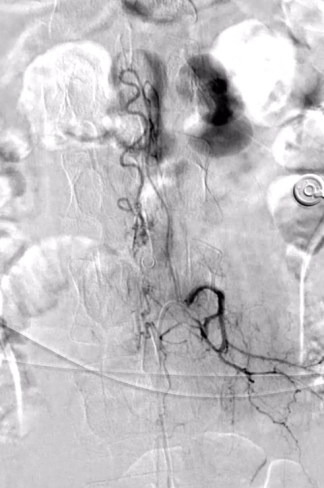

入院后,脑科郭晓宾主任团队结合其典型症状及外院核磁结果,高度怀疑脊髓圆锥占位性病变很可能为脊髓血管畸形。为明确病变性质、血供特点及与周围神经血管的关系,郭主任团队决定行全脊髓血管造影术——这一微创介入检查通过注入造影剂,在X线透视下动态观察脊髓血管形态与血流,对脊髓肿瘤、血管畸形等疾病的诊断具有关键价值。

完善术前检查、排除禁忌症,并向患者及家属充分沟通手术必要性及风险后,手术顺利开展。术中,郭晓宾主任凭借丰富经验,在局部麻醉下经股动脉穿刺插管,将导管逐一超选脊髓供血动脉,于DSA设备引导下注入造影剂,清晰显示病变为双侧腰二动脉供血动静脉畸形合并动静脉瘘,为后续治疗提供了重要依据。手术全程顺利,患者生命体征平稳,无并发症。